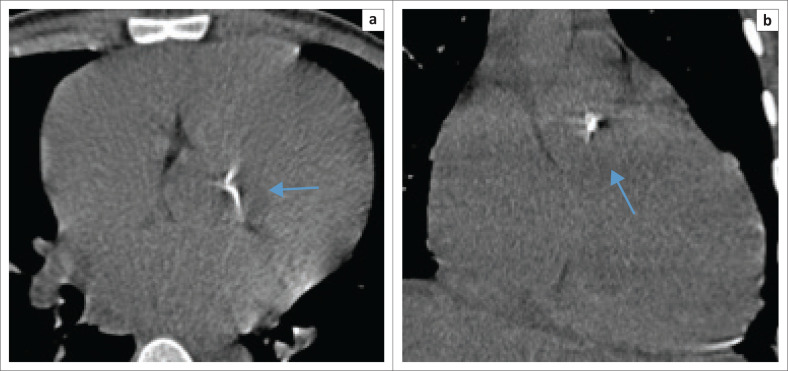

背景:国际文献报道艾滋病毒感染者(PLWH)心血管疾病患病率增加,推断其与冠状动脉粥样硬化和斑块形成加速有关。很少有当地的hiv相关心脏病研究证实了这一点。心脏斑块的早期识别将有助于临床医生进行风险分层和实施治疗策略,以降低发病率和死亡率。在资源有限的情况下,使用传统的计算机断层扫描(CT)可能在识别高危个体方面发挥作用。目的:本假设生成研究旨在通过评估心脏钙化来确定HIV对加速血管老化的贡献,在年轻HIV阳性人群中,常规CT胸部成像偶然检测到心脏钙化。方法:回顾性定量分析在夸祖鲁-纳塔尔省一家三级医院,南非,超过5年的时间。年轻患者(18-45岁)接受了不同适应症的CT胸部成像,并根据免疫状态、钙化的存在、不存在和位置进一步分类。排除艾滋病毒感染状况不明的患者。结果:心脏钙化的可能性随着年龄的增长而增加,与HIV状态无关。在队列之间没有统计学上的显著差异。在预对比子类别中,较低的p值表明“迫在眉睫”的统计显著性。造影剂可能掩盖了一些钙化。由于未能记录大量患者的免疫状态,导致他们被排除在外,限制了研究。结论:年轻hiv感染者中偶然发现的心脏钙化的患病率增加值得进一步评估和心血管风险分层。

Objectives: This hypothesis-generating study was aimed at determining the contribution of HIV to accelerated vascular aging by assessing cardiac calcifications, incidentally detected on conventional CT chest imaging, in a young HIV-positive population.

Method: A retrospective quantitative analysis was performed at a tertiary hospital in KwaZulu-Natal, South Africa, over a 5-year period. Young patients (18-45 years) who underwent CT chest imaging for varied indications were included, further sub-categorised by immune status, the presence, absence and location of calcifications. Patients with unknown HIV statuses were excluded.

Results: An increased probability of cardiac calcification with increasing age, independent of the HIV status, was established. No statistically significant difference could be demonstrated between the cohorts. In the pre-contrasted subcategory, a lower P-value suggested an 'imminent' statistical significance. Contrast may have obscured some calcifications. The failure to record the immune status in a large number of patients resulted in their exclusion and limited the study.